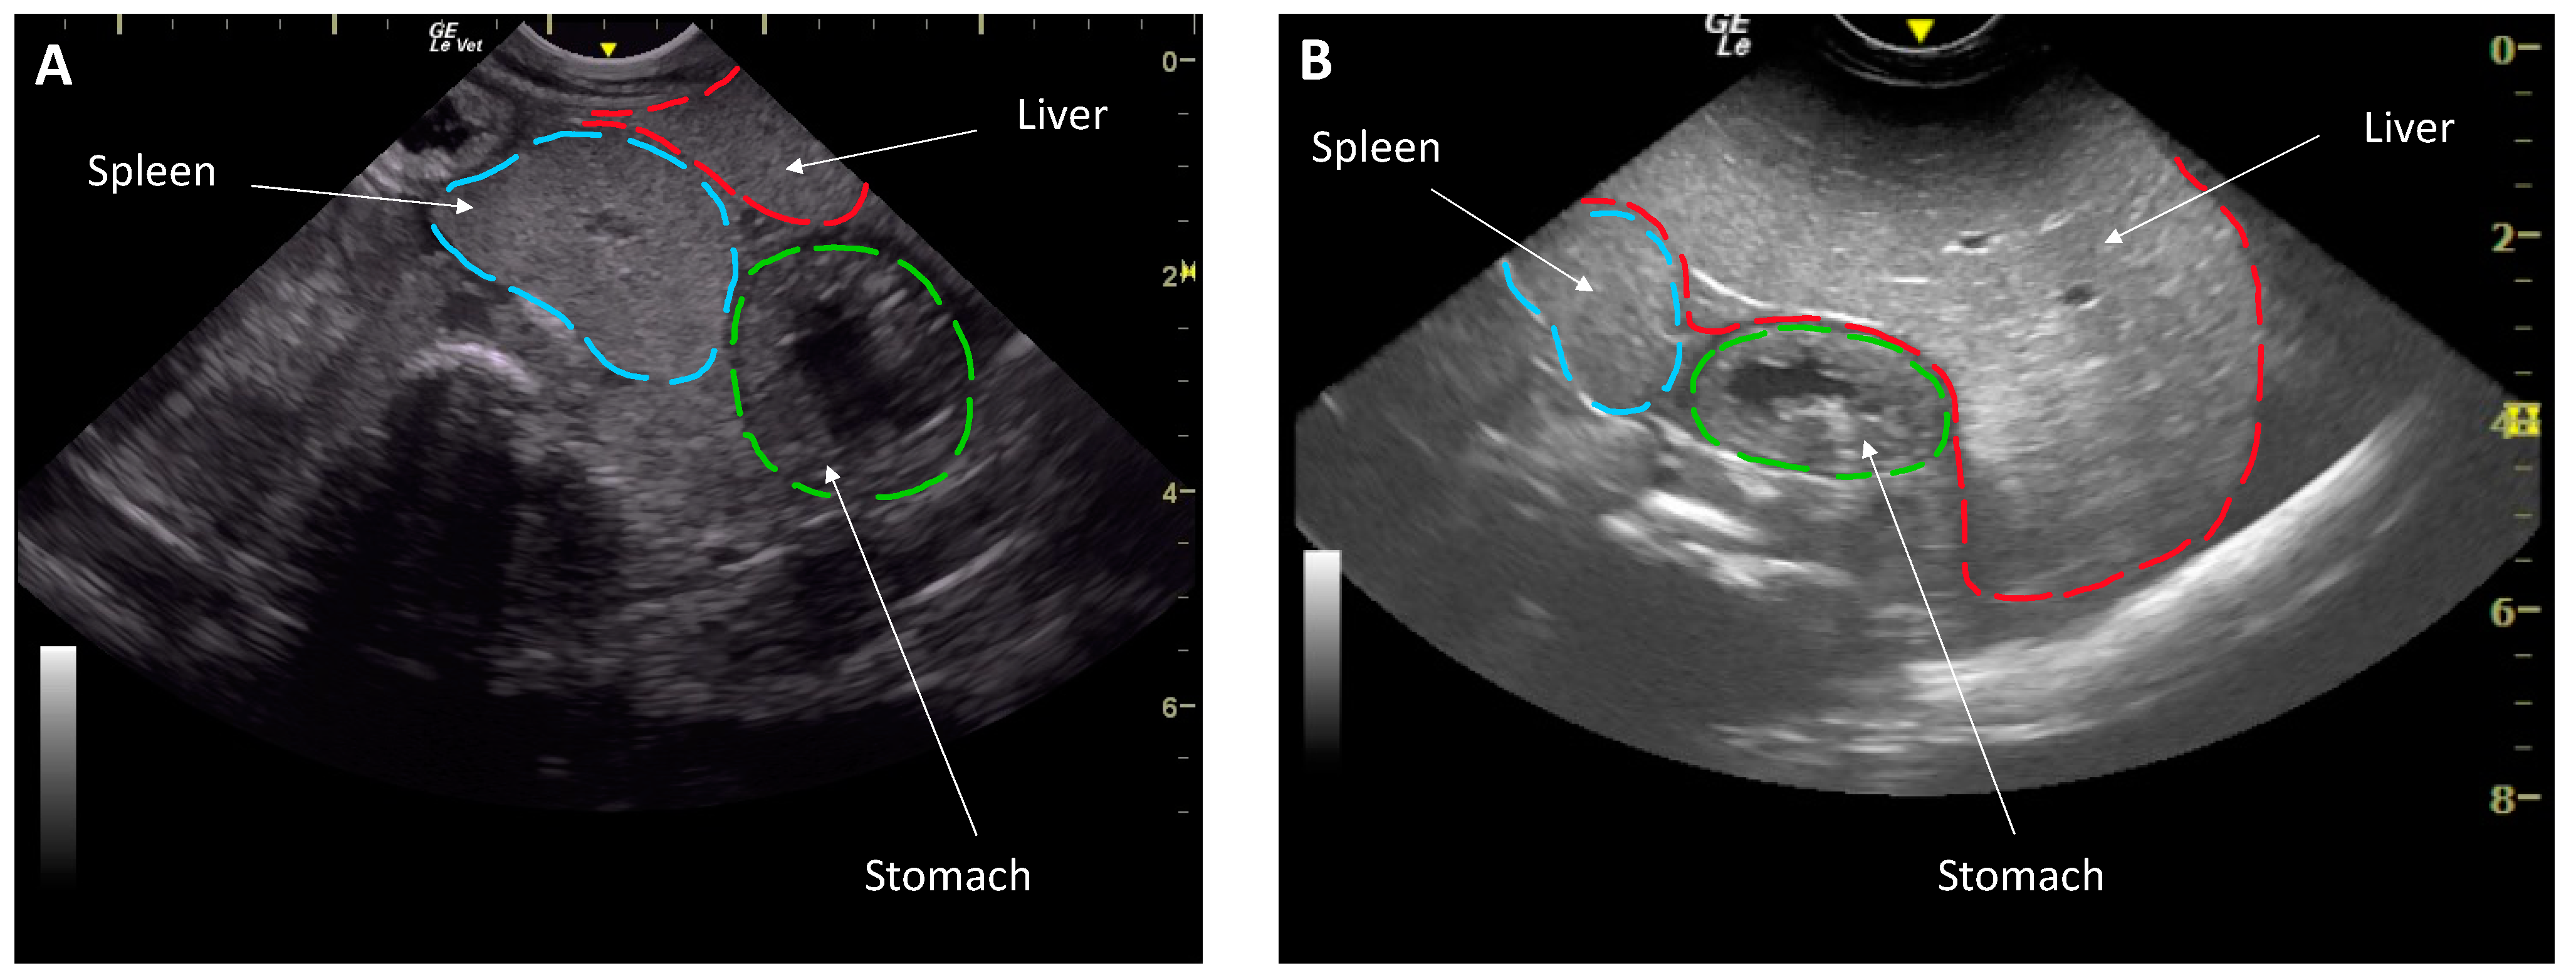

The change in body condition between health examinations offered a unique opportunity to evaluate the effect of body condition on reproductive function. Body condition was subjectively evaluated based on the appearance of the celomic fill and ultrasound characteristics [14]. Then a body condition score was assigned on a scale of 1 to 5 (1 being emaciated, 3 normal and 5 being morbidly obese) by the same researcher (N.D.M.) to eliminate inter-assessor variability. Coelomic ultrasound was performed transcutaneously in dorsal recumbency using a GE LogiqE with a 5–8 MHz curvilinear and 5–10 MHz linear transducer (General Electric Company, Boston, MA, USA) [14]. An animal of a low body condition had an ultrasound characterization that showed a small liver that spanned <50% of the coelom, had the spleen and liver thickness similar to each other and the liver and spleen were isoechogenic. Conversely, a good body conditioned animal had a liver >50% of the coelomic length, a liver that was thicker than the spleen as well as hyperechoic to the spleen (Figure 1). Average depth of the spleen in good condition was at 4 cm and <2 cm in low condition.

Figure 1.

Liver assessment by ultrasonography in a dorsally recumbent male southern stingray (Hypanus americanus) of a low body condition in March with a smaller liver (A) and an animal in good body condition June (B) with a larger liver. Note the depth of the organs illustrated by the gridlines in cm on the right.

Ultrasonography showed that all individuals had livers described as small in March and large in June, taking up ≥50% of the coelom (Figure 1). In March, increased nutrition was immediately offered and the average stingray weight in March increased by ~15%, from 6.85 ± 0.32 kg to 7.22 ± 0.28 kg in June. The body condition score similarly increased from 1.93 ± 0.07 in March to 2.93 ± 0.05 in June.